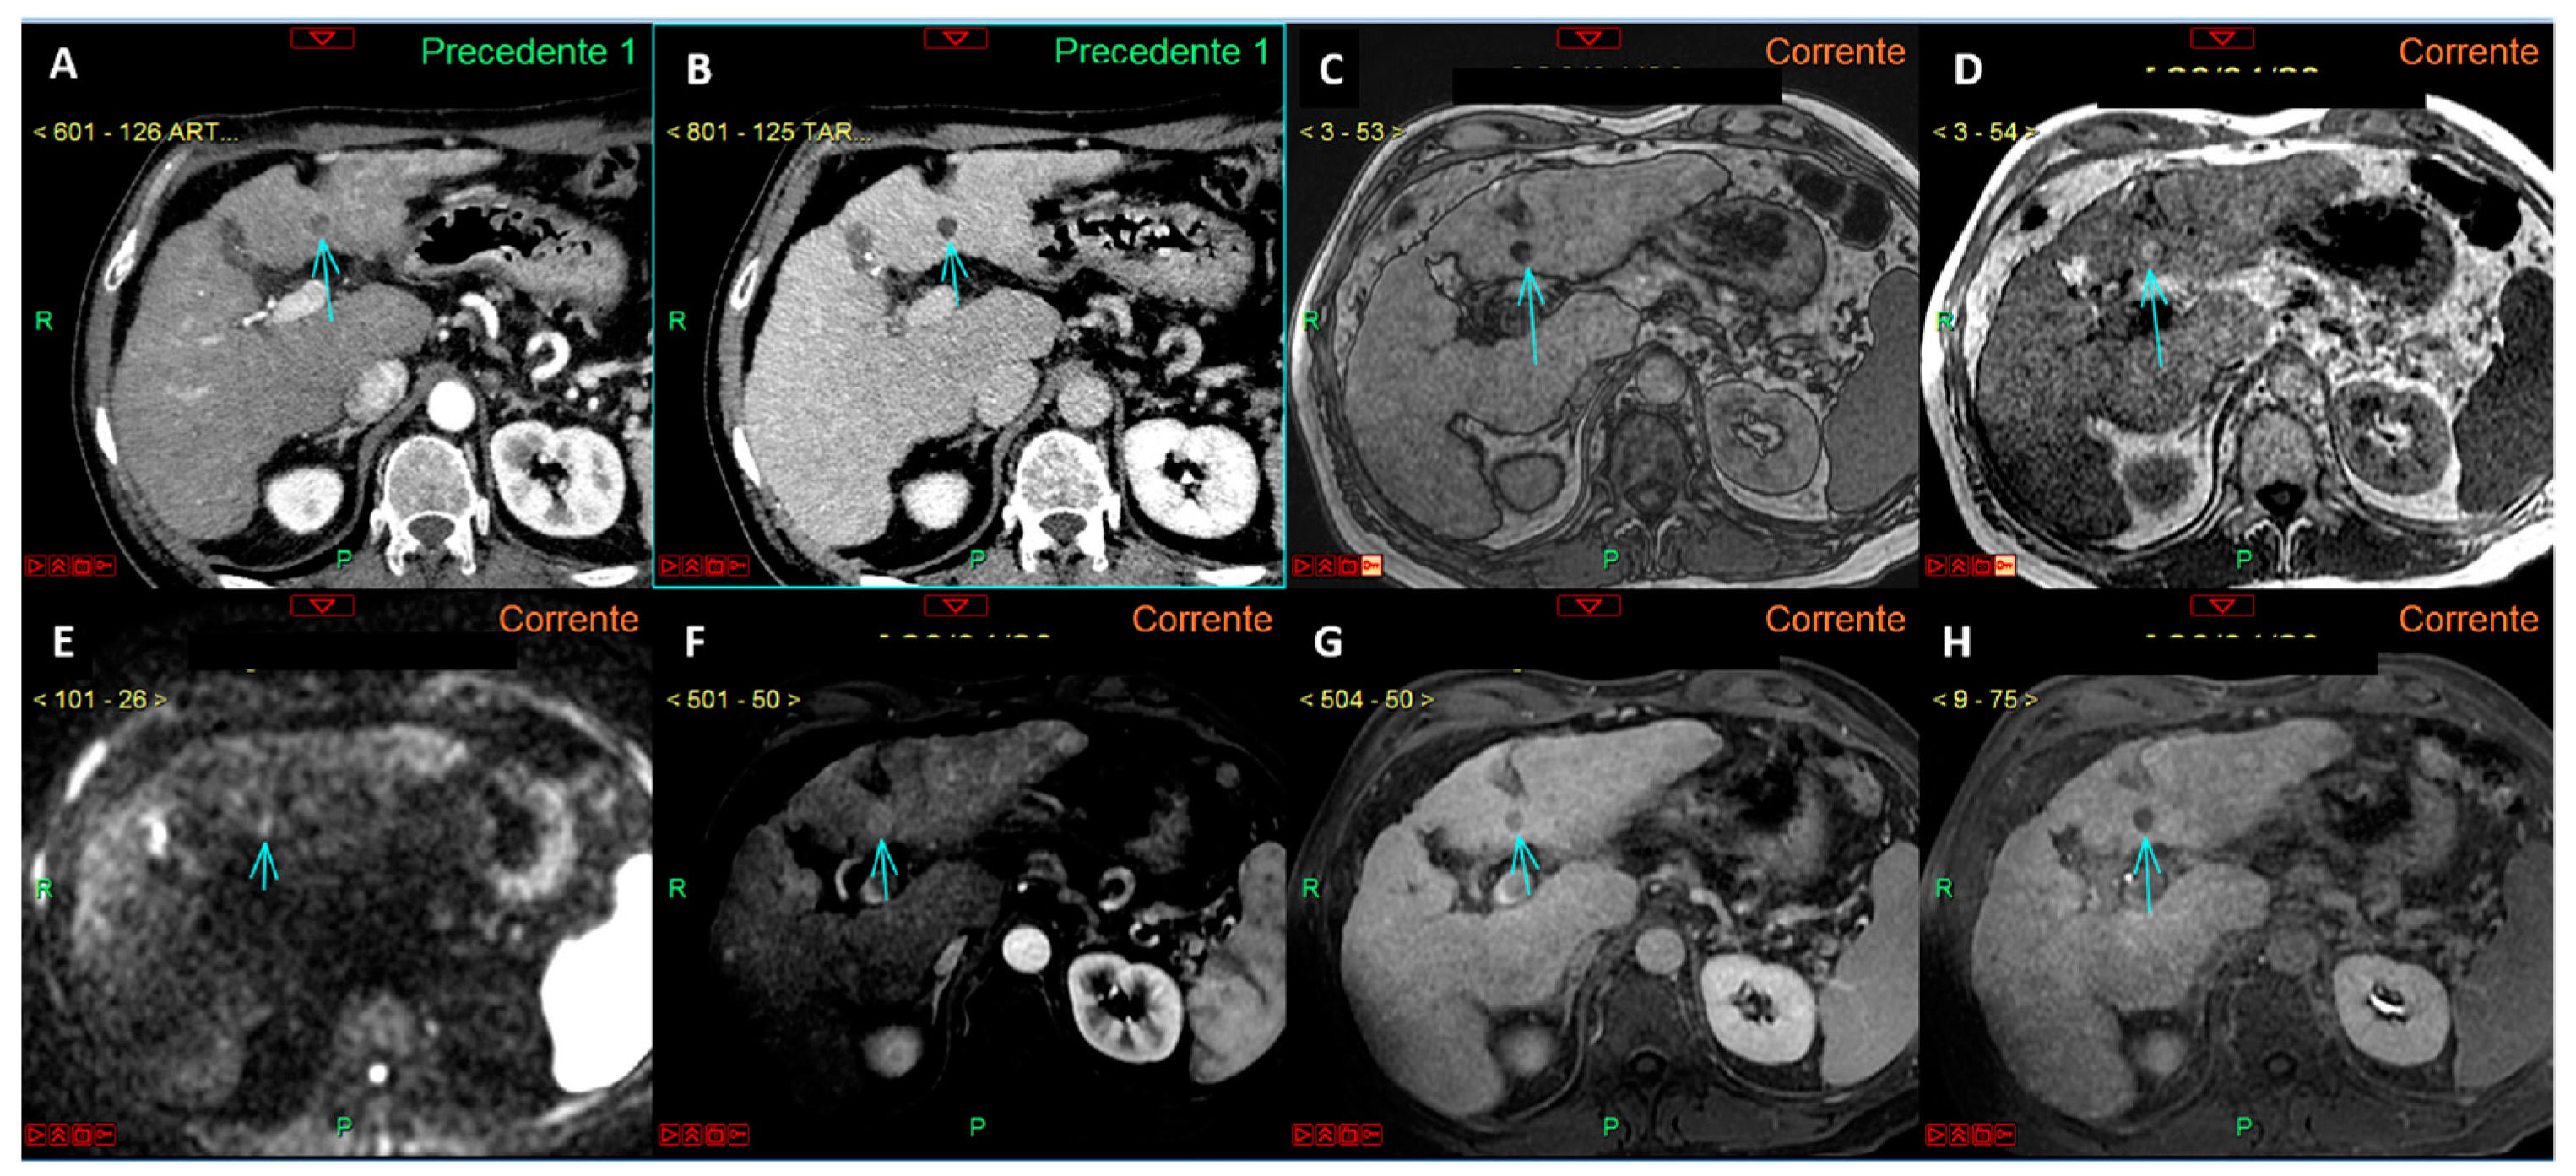

Figure 5.

CT images in the arterial (A) and delayed (B) phases show a lesion in the segment III in a cirrhotic liver (arrows in (A,B)), which cannot be accurately characterized as HCC according to EASL guidelines. In the MRI study with a hepatospecific contrast agent (arrows in (C–H)), the lesion exhibits typical features of HCC according to EASL guidelines: arterial phase hyperenhancement (F) associated with contrast media wash-out in the venous phase (G). The lesion also demonstrates additional malignant features, such as signal restriction on diffusion-weighted imaging at b-value 800 (E) and hypointensity in the hepatobiliary phase (H). According to Jiang et al. (see reference no. [31], the lesion shows homogeneous intratumoral fat, as evident from the uniform signal drop in the T1 out-of-phase sequence (C) compared to the T1 in-phase sequence (D): this feature suggests a more favorable prognosis.